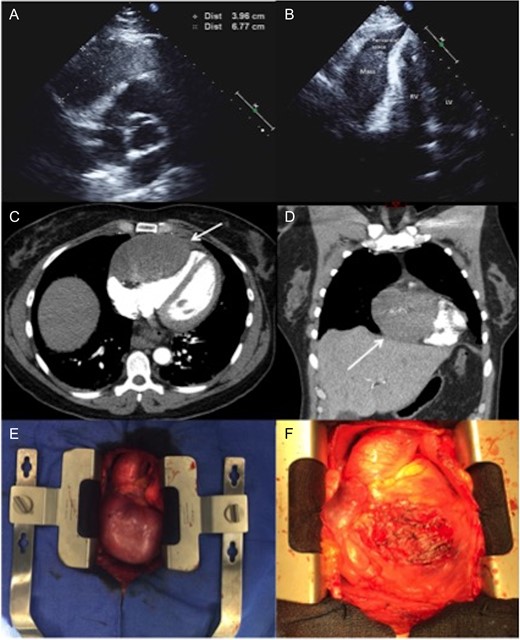

A healthy 49-year-old female with history of hysterectomy for uterine leiomyoma was referred to our hospital with tachycardia and acute onset of chest pain. On admission, the patient reported having intermittent shortness of breath and back pain for several years that significantly progressed one-week prior the presentation. The chest pain had both pleuritic and positional components, no heart murmurs or other significant clinical findings were identified. The hematological and biochemical investigations were normal. Subsequent transthoracic echocardiogram showed a round hypoechoic mass within the pericardial space. The tumor was in direct contact with the right ventricle, with no signs of local invasion. There was mild compressive effect with preserved ejection fraction of 50–55% (Figure 1). Computer tomographic (CT) angiography of the chest confirmed an 80 × 60 mm, well-circumcised solid mass of unknown origin. There was no evidence of other primary tumors or acute pulmonary thrombo-embolic disease. CT guided biopsy for tissue characterization revealed a benign spindle cell tumor. The immunohistochemical stains showed tumor cells that are strongly positive for Estrogen and Progesterone receptors (ER and PR) in addition to Smooth Muscle Actin (SMA), Desmin and Caldesmin.

(A and B) Two-dimensional echocardiography. An apical two-chamber view reveals a well-circumscribed, oval hypoechoic mass with maximal diameter of 67 mm. (C and D) Axial and coronal CTA imaging of the tumor showing the direct contact and compression effect to the right ventricle. (E)—Intraoperative pictures demonstrating a large tumor adherent to the right ventricle. (F) The heart after removing of the tumor: almost entire anterior surface of the right ventricle has been involved. LV, left ventricle; RV, right ventricle; CTA, computer tomographic angiography.